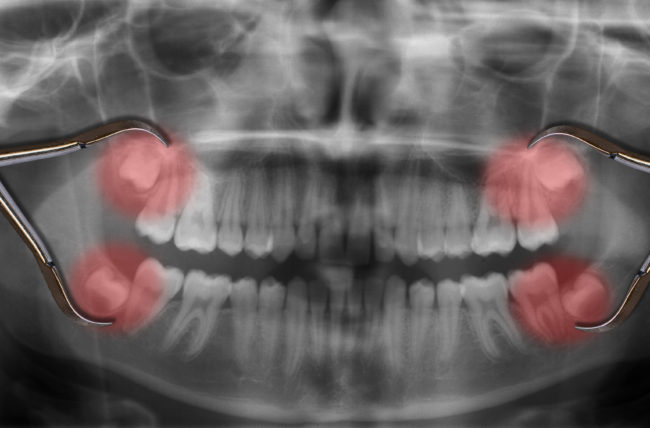

The most common reason for wisdom teeth extractions is insufficient space in the mouth. When there is not enough room for the wisdom teeth to emerge properly, they may become impacted, meaning they cannot fully break through the gum line. Impacted wisdom teeth can lead to various issues, including pain, infection, and damage to neighboring teeth.

A fluid-filled sac may sometimes form around the impacted wisdom tooth, resulting in a cyst. Cysts can damage the surrounding bone and teeth and require surgical removal.